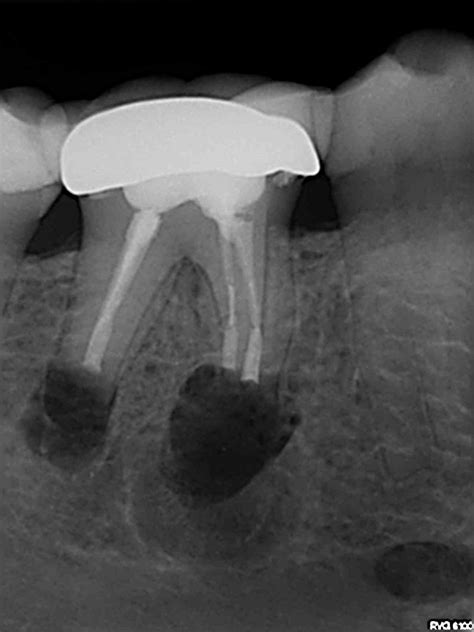

endo-surgery-2 - A2 Endodontics

endo-surgery-1 - A2 Endodontics